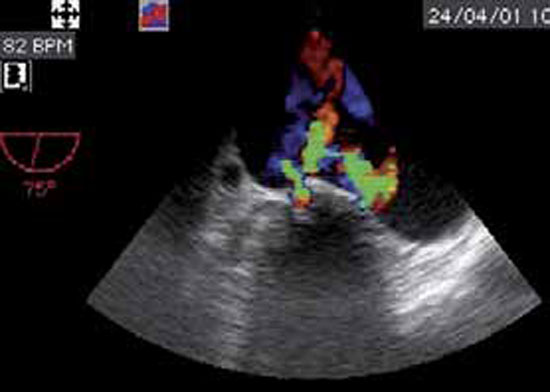

La végétation est une masse mobile, hyperéchogène, finement vibratile, attenante aux valves, et de taille variable. Elle est identifiée par l’échocardiographie transthoracique (ETT) ou l’échographie transoesophagienne (ETO) surtout en cas de prothèse valvulaire. Il faut savoir répéter l’ETO, la végétation pouvant apparaître secondairement après un premier examen normal (figures 1 et 2).

Les dégâts et la présence d’éventuelles complications sont appréciés: capotage ou désinsertion d’une valve, perforation valvulaire (figure 4), rupture de cordage, anévrysme du sinus de Valsalva.

Figure 2 : EI aortique. ETO

Volumineuses végétations sur l’ensemble des sigmoïdes aortiques.